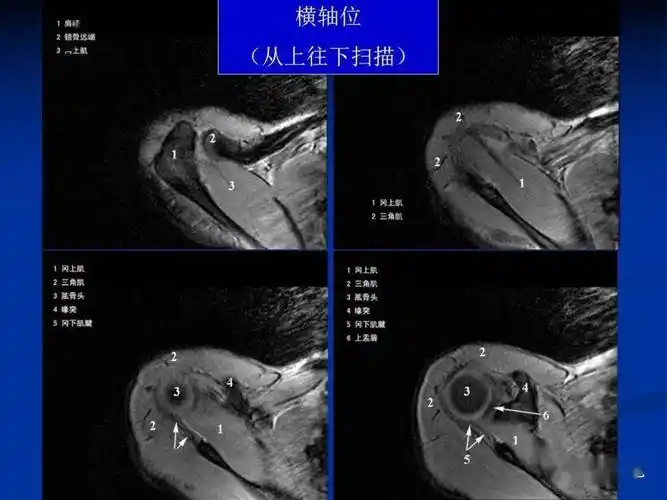

肩袖解剖及损伤的临床及mri诊断